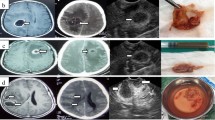

Table 1 summarizes the Mair grade of the treated pathologies. In cases of an EVD placement procedure, we assessed the ability to visualize the ventricles, which resulted grade 3 in all cases. iUS was used in 135 cases of intracranial neoplasms. All tumors were identifiable with US imaging. In 130 cases (97%), the lesion was easily and clearly visualized (Mair grades 2–3), and in just 5 cases (3%), it was difficult to identify the lesion or differentiate it from the surrounding cerebral tissue (Mair grade 1). On average, extra-axial tumors such as meningiomas, schwannomas, and craniopharyngiomas were identified more easily and had clearer limits compared to intra-axial tumors. Comparing gliomas and metastatic lesions, the latter was more discernable. Regarding gliomas, high-grade lesions (WHO III-IV) appeared to be more neatly visible than low-grade lesions: respectively 51 and 33% Mair grade 3. In high-grade gliomas, the cystic elements and the enhancing nodules are easily distinguished from the cerebral tissue. The only cases in which Mair grade was 1 were a cerebral lymphoma, a pleomorphic xanthoastrocytoma, and two multicentric glioblastomas. All four patients showed a diffuse signal alteration on preoperative MRI in both T2-weighed and FLAIR images, with a large diffusion in the respective cerebral lobes interpreted as wide disease infiltration. Fourteen cases of vascular pathologies were treated; echographic visibility was assessed: four out of five aneurysms were clearly identified with Doppler angiography (considered Mair grade 3) and one ICAOpht aneurysm was not visible probably due to proximity to the anterior clinoid process (Mair grade 0). The AVMs were visualized with Doppler angiography (Mair grade 3). Of the six deep-seated cavernous hemangiomas (4 supratentorial and 2 cerebellar) visualized with iUS, all were classified Mair grade 3; in one case with an associated hematoma, the hemangioma remained discernible even after evacuation of the hematoma despite the brain-shift. Intraparenchymal hemorrhages (6 cases) demonstrated an average low US visibility (one grade 1, four grade 2, and one grade 3) even though sufficient for localization and approach planning. Brain abscesses (2 cases) had high US visibility (Mair grade 3). Overall, regardless of histology, perilesional edema was associated with worse ability to distinguish the lesions’ limits (Fig. 2).

CECT head scan of a frontal metastasis and corresponding iUS. Posterior margin of the lesion is clearly visible on CT and iUS with a clear border with surrounding normal brain tissue (white arrow). At the medial margin, the lesion is clear on CT scan but is lacking a clear border with normal brain tissue on iUS (black arrow) due to surrounding edema (Mair grade 2)

The iUS utility in planning the trajectory to deep-seated lesions did not always correlate with the assigned Mair grade. Deep-seated extra-axial pathologies, mainly skull base tumors, although clearly visualized with iUS, were nonetheless approached through the classical surgical cisternal pathways, without the need of iUS guidance. In our experience, only one such case, a subtemporal approach to a middle temporal base meningioma, was the iUS useful during the approach. Similarly, the use of US did not impact dissection and clipping strategies during aneurysm clipping. In these patients, iUS was helpful for the placement of ventricular catheters in one case and hematoma evacuation in another one. All deep-seated intraparenchymal pathologies were approached with iUS guidance (70 patients; brain tumors, cavernous hemangiomas, hematomas, brain abscesses) (see Table 2). In these cases, iUS was used to plan a correct and safe trajectory to the lesion, avoiding major vessels (Fig. 3) and eloquent cortex (integration of iUS and neurophysiological monitoring). The transcortical approach was planned using 3D-navigated iUS in 65 patients and in five cases, a 2DiUS real-time control was used. Eight patients underwent biopsy of an intra-axial neoplasm (due to multiplicity). The target was localized with iUS and a minimally invasive approach was performed with minimal brain transgression. All the specimens were histologically positive (absence of false positive on iUS). iUS-guided EVD placement was performed in eight patients, five during shunt procedures (4 slit-ventricles and 1 malformative hydrocephalus) and three during surgery for aneurysm, hematoma, and brain abscess. Catheter placement with 2DUS real-time guidance was performed in six patients and 3DUS navigation in the remaining two patients. Correct placement was achieved in all patients.

Left panel shows axial, coronal, and sagittal view on CECT head scan of an insular glioma (Mair grade 2). Right panel shows the corresponding 3DiUS images superimposed to axial, coronal, and sagittal plans on CECT scan. The green line represents the trajectory to the target planned to avoid the vessels. Note the considerable brain-shift

Frontal glioblastoma (Mair grade 3). a 3DiUS acquisition prior to resection: axial, coronal, and sagittal plan superimposed to the corresponding preoperative CT head scan. b–d Progressive tumor debulking with contemporary display of tissue and power Doppler signal (note the position of the anterior cerebral artery with respect to the cavity wall)

In our experience, a decrease in echographic visibility was encountered during intraparenchymal hematomas evacuation. The iUS was used to plan the transcortical trajectory, but in all six patients, we could not evaluate the progression of evacuation, with an average of one grade-lowering on the Mair classification. Power Doppler angiography was used to localize major vessels encased or adjacent to the lesion and major feeding arteries (tumors, AVMs). Displaying simultaneously iUS tissue signal and power Doppler allowed us to localize and spare vascular structures during both the approach and the resection (Fig. 5). Repeated intraoperative Doppler acquisitions were also used to check progressive deafferentation of AVMs and hypervascularized tumors. On the opposite of the tissue signal, we did not observe any decrease of the Doppler images’ quality throughout the procedure.

Echographic visibility of brain lesions is difficult to be objectively quantified. There is a well-known learning curve of interpreting and recording iUS images and there can be various artifacts in surgical cavities that contribute to a deterioration of ultrasound image quality and lesion delineation during resection [12]. We used an echographic visibility grading system proposed by Mair et al. in 2013 [8]. It is a four-tiered system that takes into account the echogenicity of the lesion and its border visibility (Fig. 1). Although it is an unvalidated scale, it is almost identical to others [14, 16]. Similar to what other authors have described [8, 11, 17, 21, 22], all lesions, except one aneurysm, were identifiable by iUS. Most of the lesions (primary and metastatic tumors, cavernous hemangiomas, abscesses) appear hyperechoic compared to the surrounding normal brain parenchyma. Edema also appears slightly hyperechoic. Hemorrhage has different echogenic aspects, depending on the phase of the bleeding: in the acute phase, for example, it appears hyperechoic. Extra-axial and metastatic tumors were on average identified more easily and had clearer limits compared to intra-axial tumors. Among the latter, diffusely infiltrating lesions showed the lowest grade of visibility with poor limits of definition (Table 1). Depiction of tumor borders was dependent on intrinsic factors (nature of the lesion) and extrinsic factors (surrounding parenchyma). Considering intrinsic aspects, diffuse infiltrative lesions (such as infiltrative gliomas and lymphomas) do not have a histologically defined border and echographic differentiation from normal brain is difficult; extra-axial lesions (i.e., meningiomas and hemangiomas) on the other hand have a well-defined anatomical (hence echographic) demarcation with normal parenchyma [2]. Brain metastases are also usually well circumscribed and have a defined border on MRI and in the corresponding ultrasound images [2, 8, 22]. Extrinsic features refer to perilesional edema or hemorrhage that, being slightly hyperechogenic, reduce the contrast between the hyperechogenic signal of the lesion and the signal of the brain (Fig. 2). For this reason, diffusely infiltrating lesions with poor edema might be better visualized than high-grade lesions with perilesional edema. For the same reasons, a meningioma or hematoma with surrounding edema could appear less definable [2, 22, 23]. In high-grade gliomas, although infiltrative in nature, iUS is capable of identifying different multiform portions of the solid lesion such as necrosis, cysts, bleedings, and irregular dense tumor. Again, visibility improves as perilesional edema decreases.